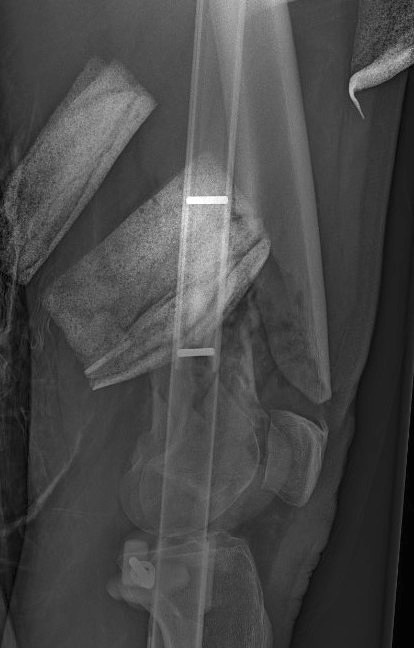

Retrograde Nail

Surgical Technique

Pass guide wire

- consider blocking screws to aid reduction

- can use femoral distractor

Blocking screws

Femoral distractor and retrograde nail

Locking screws

- distal locking performed with jig

- proximal AP locking under xray control